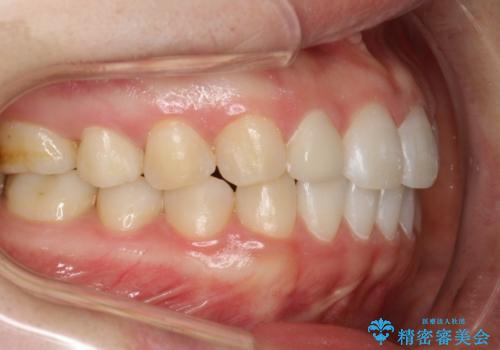

Invisalign インビザライン lite ライト 隙っ歯の改善

- 20代女性

- invisalign lite

- 6ヶ月

- マウスピース矯正による隙間の閉鎖を計画しました。

簡便な処置のため、ライトを選択しました。

かみ合わせが深くない空隙歯列は、最も簡単にその改善が見込まれます。